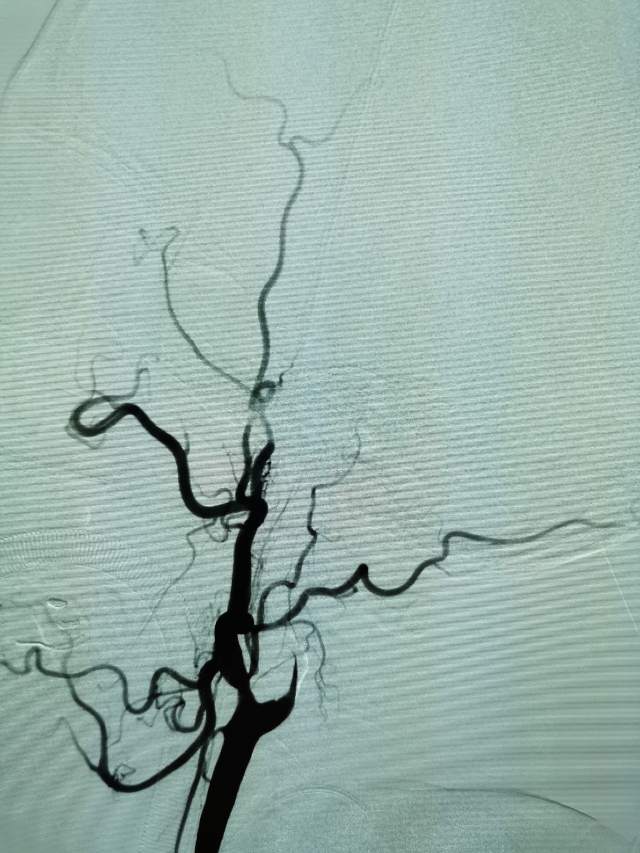

儿子很是着急,多方打听后,转来我院。入院后的评估发现左侧颈内动脉已经闭塞2个月了,左侧的大脑半球“红彤彤”的一大片,就像燃烧的“火焰山”。处于严重的缺血状态,人怎么可能有活力呢~

今日,我们重新为患者开通闭塞的血管,术后,患者重新焕发勃勃生机,俨然换了一个人~~~